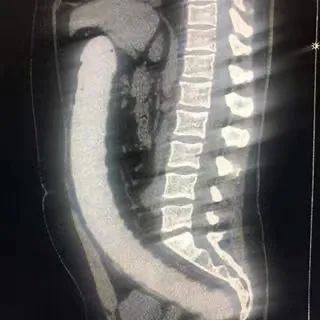

前两天,湖北一名30多岁的冯先生,因寻刺激把按摩球塞入了肛门,不料一堵就是两天取不出,不得不到专门的肛肠医院就医。

值得一提的是,这已经是冯先生第三次因为往肛门里塞东西进医院,可谓是经验丰富。更巧合的是,每一次都是同一位医生接诊,据这位医生介绍,他曾从冯先生体内取出过花露水瓶、小油壶,这次塞进去的按摩球尺寸比成年人拳头还要大,通过手术把按摩球分解后,这才得以取出。